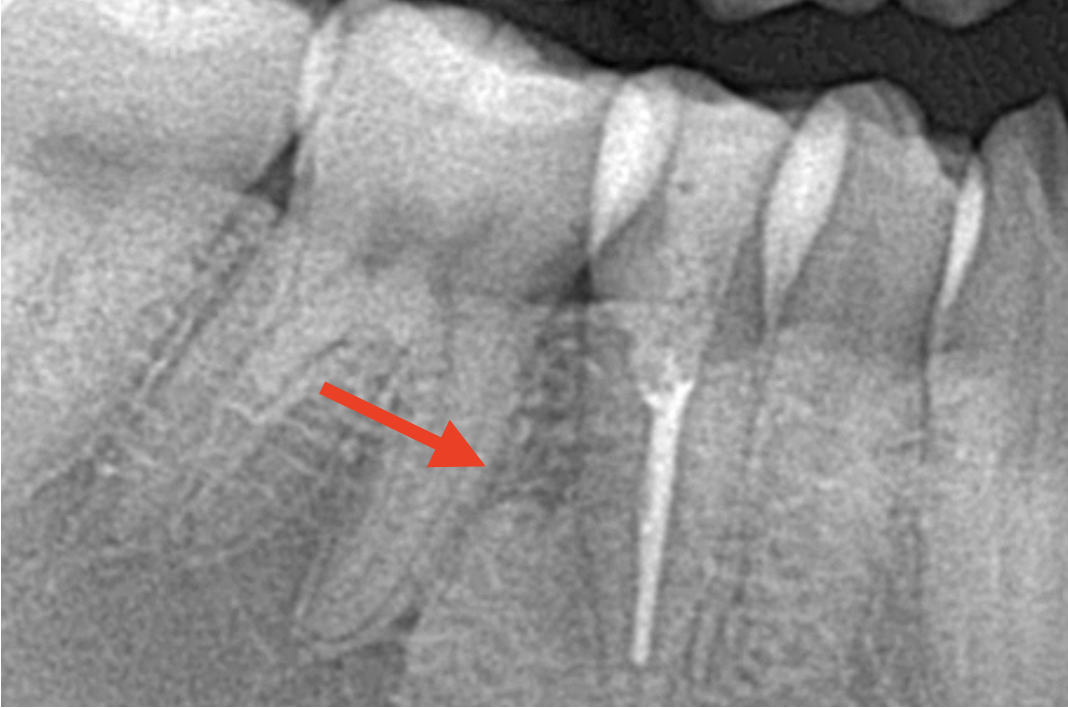

従来、歯や歯肉の内部の状態は、レントゲンで確認されてきました。しかし入り組んだ根管などは、レントゲンでは把握しにくいのが実情です。

そこで用いられるのが、歯科用のCTです。歯科用CTを用いると、歯・歯肉の内部、顎骨といった口腔全体の詳細な状態を、三次元的に把握することが可能です。レントゲン画像では重なり合ったり、不鮮明に映し出されていた根管も、歯科用CTでは鮮明に、あらゆる角度から構造を確認することができます。

これによって、診査・診断の精度は飛躍的に向上します。

大きな根尖病変を根管治療にて治療し、歯を残した症例

- 年代、性別 26歳・女性

- 来院動機 右下で噛むと違和感がある

- 治療内容 精密根管治療

- 治療期間 来院回数3回、治療期間は3週間